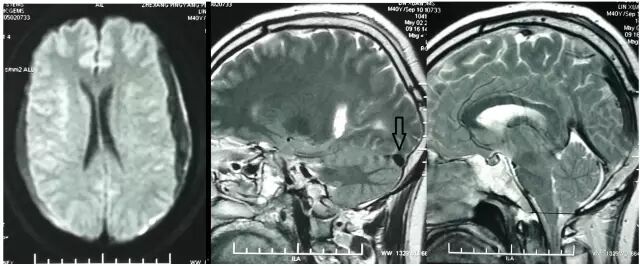

除了临床特异性的表现外,在影像学方面,SIH患者的颅脑MRI有5个典型特征(SEEPS):

(1)Subduralfluid collections硬膜下积液;

(2)Enhancement of the pachymeninges硬脑膜强化;

(3)Engorgement of venous structures静脉结构充盈 ;

(4)Pituitaryhyperemia垂体充血;

(5)Sagging of the brain脑组织下沉。其中又以硬脑膜强化及硬膜下积液最为常见。

图10. 典型病例增强MRI:硬脑膜强化合并双侧硬膜下积液。

图11. A为正常的横窦,B为扩张的横窦。

图12. A为正常脑组织矢状位,B可见脑组织下坠。